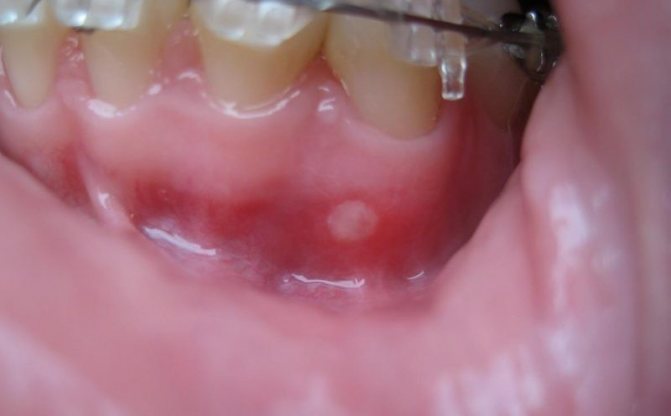

- Герпетическая инфекция поражает кожные покровы, оболочки, внутренние органы. Герпетический стоматит проявляется многочисленными мелкими язвами, которые располагаются группами на дне ротовой полости.

- Герпетиформный стоматит. Для этой патологии характерны небольшие ранки серого цвета со слабо очерченными границами. Чаще всего появляются в нижней части ротовой полости, нанося вред слизистой оболочке. Есть вероятность распространения на подъязычный участок. Пораженная область заживает относительно быстро – достаточно всего недели.

- Стоматит герпетиформного характера. Язвы при таком заболевании очень часто похожи на герпес. Обычно они локализуются на языке и на дне ротовой полости. Обычно исчезают спустя несколько дней. Но когда раны не заживают самостоятельно, необходимо обратиться за медицинской помощью.